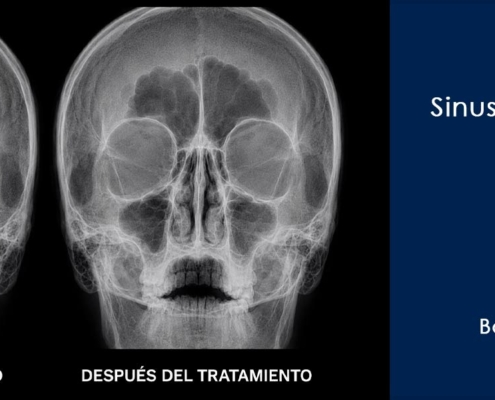

DMT_ADM_FIS_242026-06-12 08:55:032026-06-12 08:55:03Tratamiento con bomba diamagnética en sinusitis frontal bilateral recurrente

DMT_ADM_FIS_242026-06-12 08:55:032026-06-12 08:55:03Tratamiento con bomba diamagnética en sinusitis frontal bilateral recurrenteEjemplos reales de Terapia Diamagnética

La terapia diamagnética ha revolucionado la manera en que tratamos diversas afecciones, desde lesiones deportivas hasta dolencias crónicas. En esta página, encontrarás una recopilación detallada de casos clínicos de terapia diamagnética, mostrando cómo este tratamiento innovador ha ayudado a nuestros pacientes a mejorar su calidad de vida.